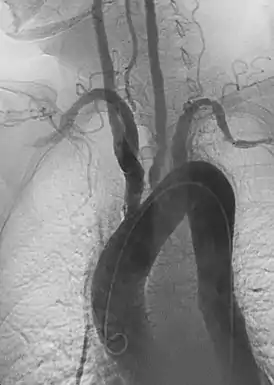

Синдро́м Такая́су (неспецифи́ческий аортоартерии́т)[* 1] — аутоиммунное воспалительное заболевание, поражающее аорту и её ветви[4]. Относится к группе системных васкулитов, характеризуется развитием в стенке крупных артерий продуктивного воспаления, ведущего к их облитерации. Случаи заболевания фиксируются повсеместно, однако наиболее предрасположены к нему молодые женщины[4]. Соотношение заболевших женщин и мужчин составляет 8:1, а проявляется болезнь обычно между 15-ю и 30-ю годами.

Приблизительно у половины пациентов обнаруживаются первичные соматические симптомы: недомогание, лихорадка, расстройство сна, потеря веса, боль в суставах и утомление. Часто сопровождается анемией и повышением скорости оседания эритроцитов. Эта стадия постепенно спадает и переходит в хроническую стадию, характеризующуюся воспалительными процессами в аорте и её ветвях. У другой половины больных синдромом Такаясу обнаруживаются лишь поздние изменения сосудистой системы, без предварительных соматических симптомов. На поздних стадиях слабость стенок артерий может привести к возникновению локализованных аневризм. Также синдром обычно вызывает у пациента феномен Рейно.

Выделяют четыре типа поздних стадий синдрома Такаясу, характеризующих участки поражения:

- Первый тип — Поражается только дуга аорты и отходящие от неё артерии

- Второй тип — Поражается только грудной и брюшной отдел аорты

- Третий тип — Поражается дуга аорты совместно с грудным и брюшным отделом

- Четвёртый тип — К поражению при предыдущих трех типах добавляются патологические изменения в легочной артерии